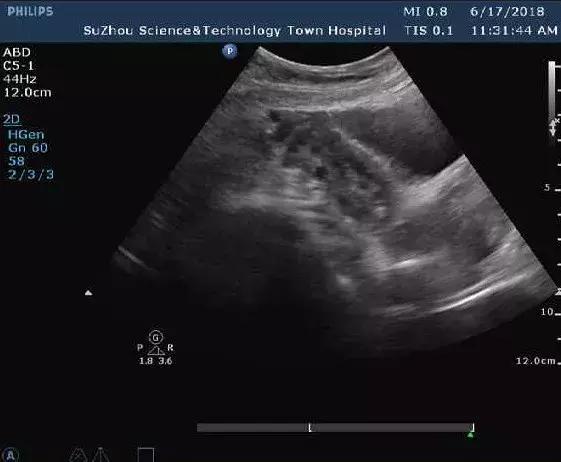

而“卵巢多囊样改变”则是指在卵泡早期超声检查一侧或双侧卵巢直径2~9mm的卵泡超过12个或卵巢体积超过10ml。据临床调查研究发现,在正常女性当中也有有20%-30%同时伴有卵巢多囊样改变,但不代表她们就是有多囊卵巢综合征。